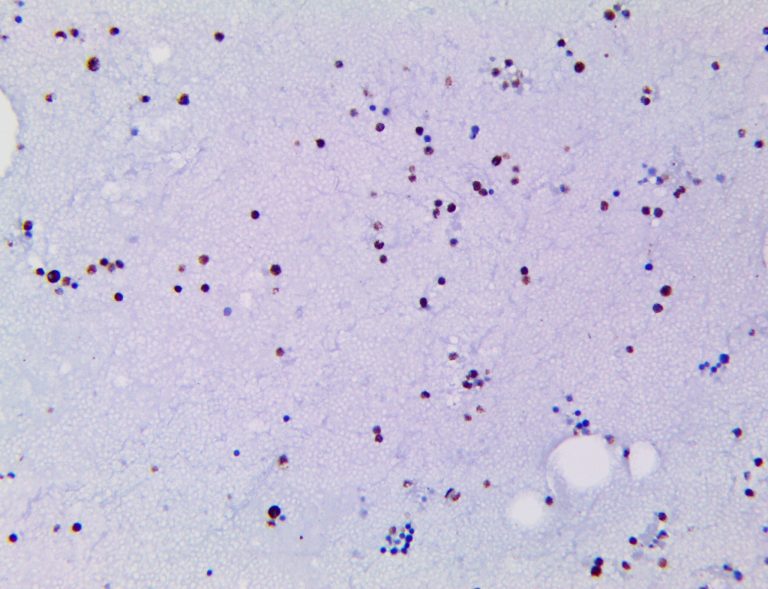

It is the ICU physician who is most likely to witness one of the deadliest manifestations of the abnormal immunological response, the cytokine storm syndrome (CSS). This response is also referred to by some as the cytokine release syndrome (CRS). CSS is characterized by continuous activation and expansion of macrophage and lymphocyte populations, which secrete large amounts of cytokines, causing the cytokine storm. This massive cytokine release is akin to hemophagocytic lymphohistiocytosis (HLH) disease, a syndrome characterized by initial unchecked and persistent activation of cytotoxic T lymphocytes and NK cells.

Clinical and laboratory manifestations of HLH include fever, enlarged liver and/or spleen, neurologic dysfunction, coagulopathy, liver dysfunction, cytopenias (i.e., low levels of erythrocytes, leukocytes, and/or platelets), hypertriglyceridemia, hyperferritinemia, hemophagocytosis, and eventually diminished NK cell activity as the immune system becomes progressively paralyzed. HLH can be familial (primary HLH) or secondary to another disease process (sHLH), such as rheumatic disease, in which it is referred to as macrophage activation syndrome (MAS, characterized by elevated ferritin).